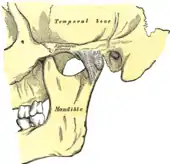

Temporomandibular joints

The temporomandibular joints are the dual articulation of the mandible with the skull. Each TMJ is classed as a "ginglymoarthrodial" joint since it is both a ginglymus (hinging joint) and an arthrodial (sliding) joint,[41] and involves the condylar process of the mandible below, and the articular fossa (or glenoid fossa) of the temporal bone above. Between these articular surfaces is the articular disc (or meniscus), which is a biconcave, transversely oval disc composed of dense fibrous connective tissue. Each TMJ is covered by a fibrous capsule. There are tight fibers connecting the mandible to the disc, and loose fibers which connect the disc to the temporal bone, meaning there are in effect 2 joint capsules, creating an upper joint space and a lower joint space, with the articular disc in between. The synovial membrane of the TMJ lines the inside of the fibrous capsule apart from the articular surfaces and the disc. This membrane secretes synovial fluid, which is both a lubricant to fill the joint spaces, and a means to convey nutrients to the tissues inside the joint. Behind the disc is loose vascular tissue termed the "bilaminar region" which serves as a posterior attachment for the disc and also fills with blood to fill the space created when the head of the condyle translates down the articular eminence.[42] Due to its concave shape, sometimes the articular disc is described as having an anterior band, intermediate zone and a posterior band.[43] When the mouth is opened, the initial movement of the mandibular condyle is rotational, and this involves mainly the lower joint space, and when the mouth is opened further, the movement of the condyle is translational, involving mainly the upper joint space.[44] This translation movement is achieved by the condylar head sliding down the articular eminence, which constitutes the front border of the articular fossa.[35] The function of the articular eminence is to limit the forwards movement of the condyle.[35] The ligament directly associated with the TMJ is the temporomandibular ligament, also termed the lateral ligament, which really is a thickening of the lateral aspect of the fibrous capsule.[35] The stylomandibular ligament and the sphenomandibular ligament are not directly associated with the joint capsule. Together, these ligaments act to restrict the extreme movements of the joint.[45]